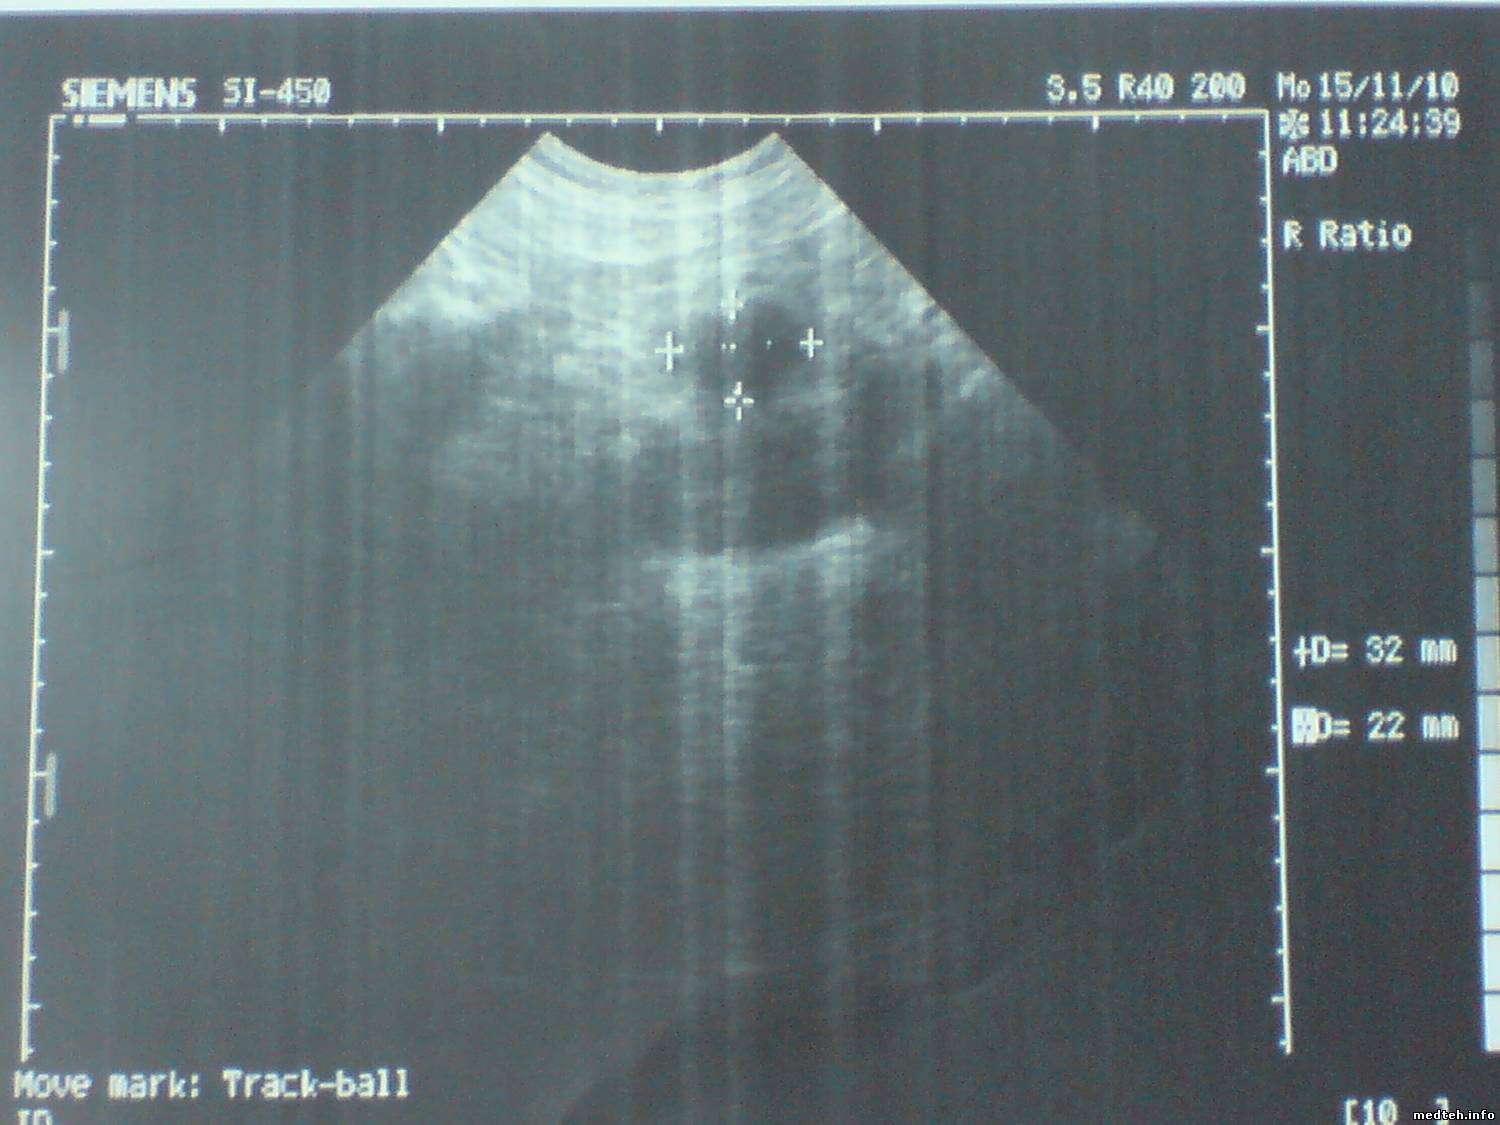

Датчиком которым смотрит щитовидку - изображение удволитворительное а

Quote (РОМУЛ)

картинка на линейке 7,5 МГЦ действительно не очень,

тут какраз и проблема.Посмотрите - есть снимки

1284362.jpg (112.9 Kb) · 7186455.jpg (91.8 Kb) · 3431615.jpg (125.3 Kb)

То, что я вижу,- это снимки снимков с принтера. И это дефекты самого принтера, а никак не аппарата, нужно фото именно с экрана, и с хорошим качеством, без фспышки. Тогда можно будет о чем-то говорить.